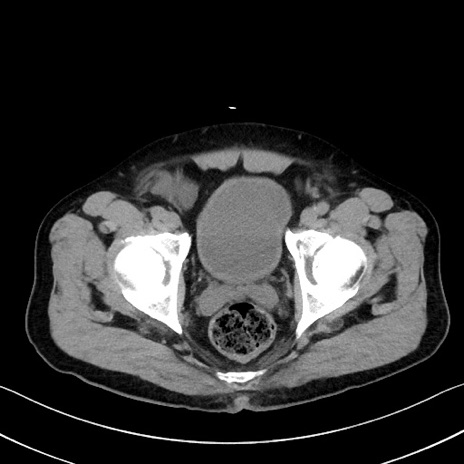

症例35(横断像)

【症例】70歳代 男性

【主訴】腹部膨満、嘔吐

【現病歴】昨日より腹部膨満感出現。本日増悪し、仙痛出現。嘔吐あり、受診。

【既往歴】糖尿病、胆摘後

【身体所見】BP 149/80mmHg、HR 74/min、BT 35.9℃、腹部:膨満、軟、圧痛なし。腸雑音減弱あり。上腹部正中切開瘢痕あり。

【データ】WBC 13500、CRP 1.72

冠状断像